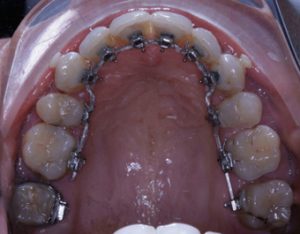

En Lingual : sur la face interne des dents

Arcade maxillaire avant traitement orthodontique, séquelles de maladie parodontale

Après traitement orthodontique et réalisation d’une attelle coulée collée (courtoisie Dr Patrick Fournier)